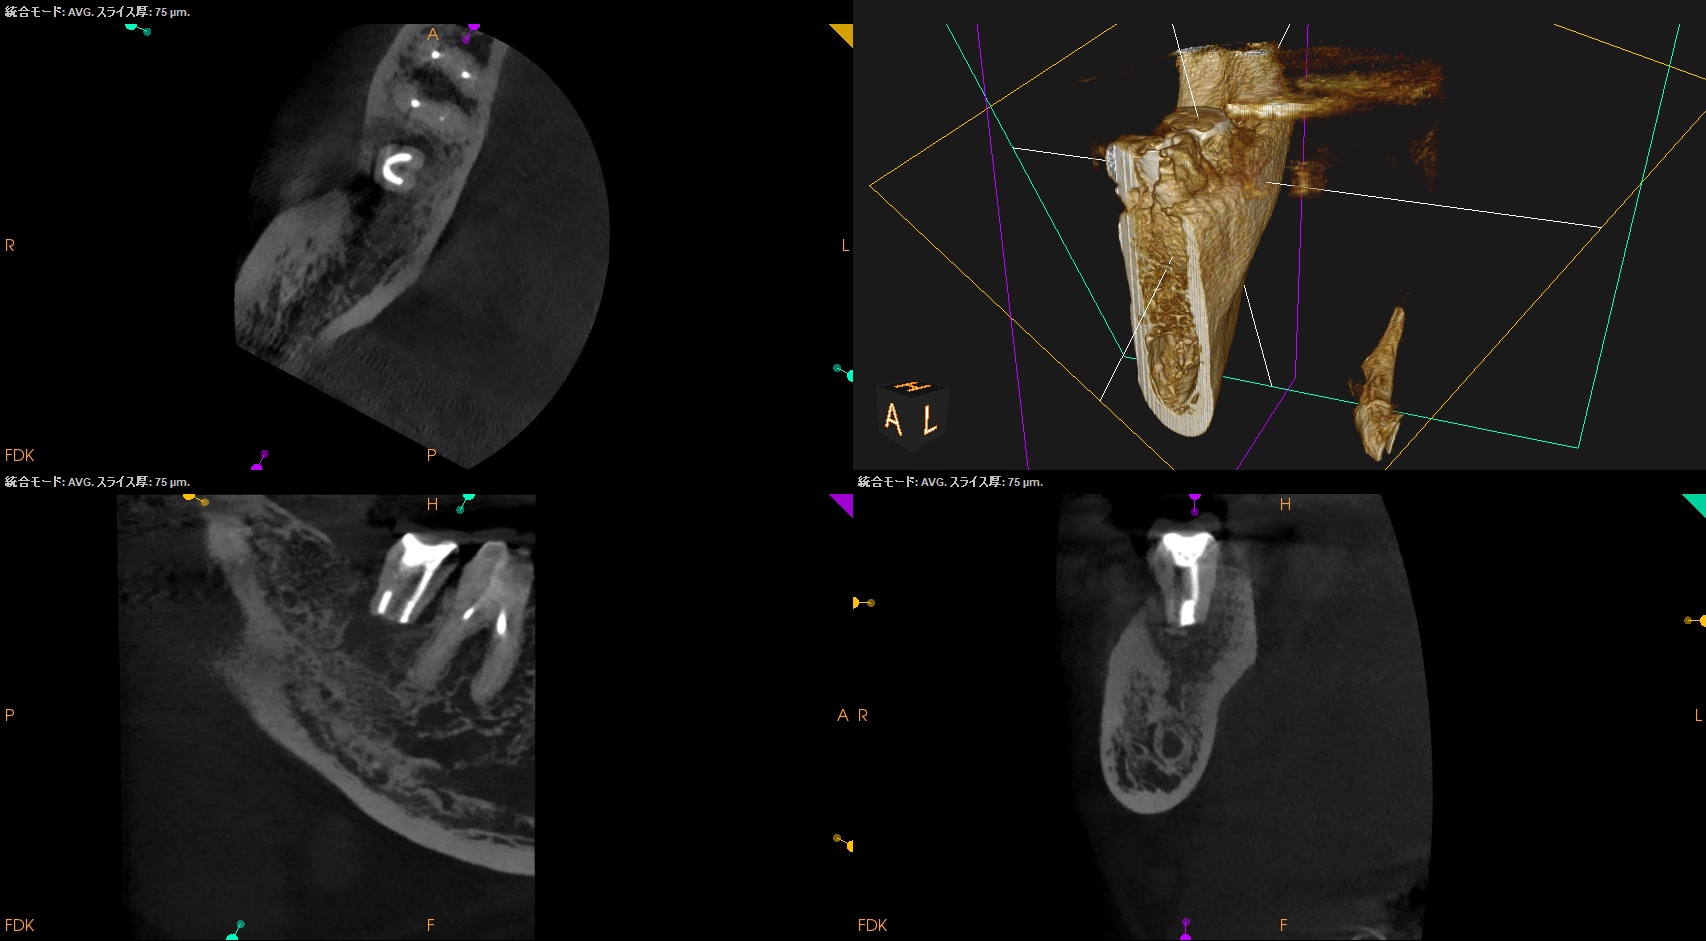

CBCT(2025.5.19)

ML

MB

D

確かに…

折れていると言われかねない状況だ。